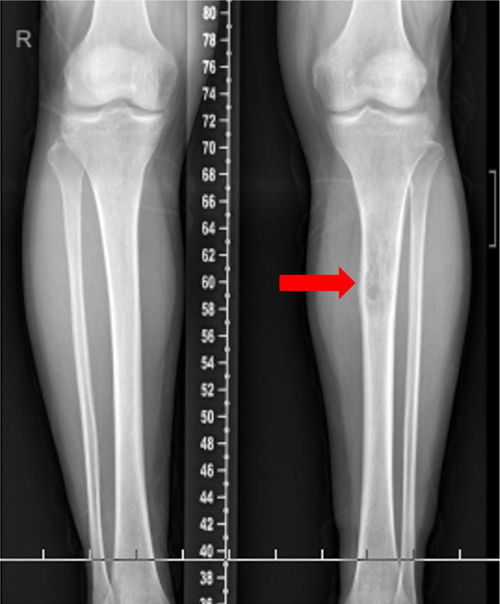

骨嗜酸性肉芽肿-骨溶骨性破坏,良性

骨嗜酸性肉芽肿——一种表现为溶骨性破坏的良性骨病探究 骨嗜酸性肉芽肿是一种以骨骼系统局限性溶骨性破坏为特征的良性病变,本质为朗格汉斯细胞的克隆性增生。本文系统阐述了该病的流行病学特征、病因假说、病理基础、临床表现与影像学特点,重点分析了其“良性溶骨性破坏”的独特性质,并综述了当前的诊断标准、鉴别诊断要点、个体化治疗策略及总体良好的预后,旨在深化临床及公众对这...